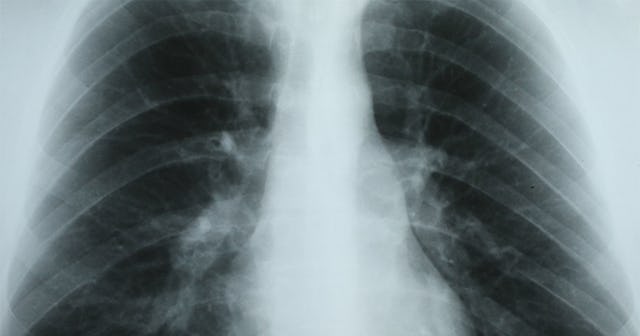

Cancer is a horrible beast, and I don’t know anyone who hasn’t been affected by it in some way. Lung cancer, in particular, is one of the worst cancers out there. It’s one of the most common cancers—the second most common cancers in men and women, according to the American Cancer Society. It’s also one of the most deadly cancers: 131,880 adults died from lung cancer in 2021.

Part of the reason lung cancer is so deadly is that it’s often in an advanced state before symptoms emerge. Not only that, but often, the symptoms of lung cancer don’t even involve the lungs, which can make it harder to detect and diagnose. In fact, there’s a type of lung tumor called a Pancoast tumor that very rarely causes symptoms in the lungs. Its symptoms involve your shoulders, arms, hands, face, and eyes.

According to WebMd, Pancoast tumors are usually a type of non-small cell lung cancer (NSCLC). They form at the top of one your lungs, and are likely to invade the surrounding tissue. Instead of directly affecting your lung tissue, they often involve your chest wall, and can spread to your lymph nodes, spine, ribs, and nerves.

Like other lung cancers, Pancoast tumors can be caused by smoking, secondary smoke, asbestos exposure, and exposure to industrial chemicals. It’s because of the way that they can affect your nerves and spine that they end up causing all kinds of weird, non-lung specific symptoms.